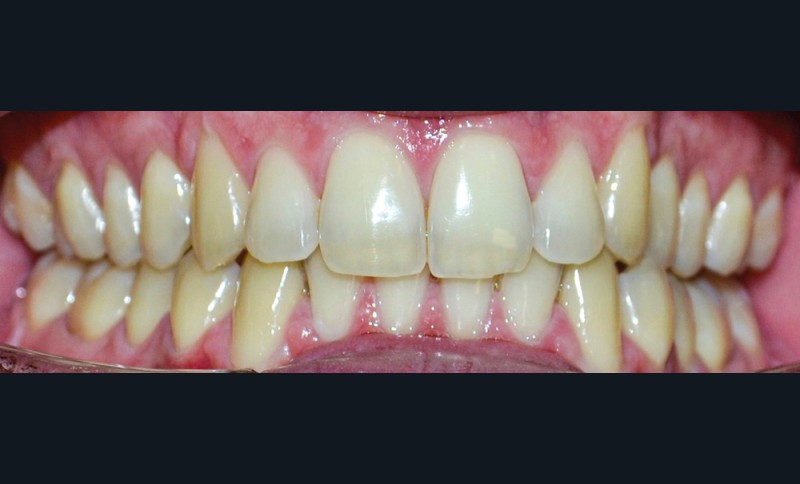

► L’entretien semi-directif met en évidence des signes d’apparition récente (un an environ), une aggravation progressive des symptômes, et la perception rapportée par le patient de moindres contacts occlusaux du côté gauche. L’examen clinique extra-oral révèle des douleurs musculaires lors de la palpation des muscles masséters, temporaux et ptérygoïdien médial gauche ainsi que des muscles sterno-cléïdo-occipito-mastoïdiens droit et gauche. Il n’y a pas de limitations d’ouverture buccale. L’examen clinique intra-oral révèle la présence d’une inocclusion dentaire gauche, qui s’étend des dents 23 à 27 (fig. 1 et 2). Il est à noter que la reprise de l’entretien ne rapporte pas d’antécédent de soins dentaires, orthodontiques et/ou prothétiques susceptibles d’engendrer une modification de l’occlusion.